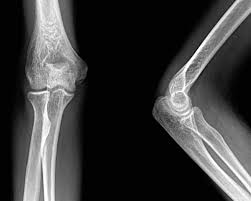

Man spricht dann von Osteochondrosis dissecans kurz. Die schmerzhafte Entzündung führt auch zur Knorpelerweichung und zum Knorpelabbau in den Gelenkflächen des Ellenbogengelenks. Wenn das Knochenfragment sich ins Gelenk verlagert besteht die Gefahr der akuten Einklemmung Knorpelschädigung und später einer Arthrose.

Stechende Schmerzen und Bewegungseinschränkungen im Ellenbogen können durch freie Gelenkkörper im Ellenbogen verursacht werden. Am Ellenbogen verlaufen zwei größere Nerven. Die Betroffenen verspüren bei Belastung des Ellenbogens oder auch in Ruhehaltung Schmerzen.

Die beiden häufigsten Ursachen sind ein Sturz und eine Entzündung der dort ansässigen Schleimbeutel. Wenn bei bestimmten Bewegungen oder sogar im Ruhezustand Schmerzen an der Außenseite des Ellenbogens auftreten dann kann es sich um einen sogenannten Tennisellenbogen handeln. Durch einen Knochensporn entstehen Schmerzen und Taubheitsgefühle am Ellenbogen.

Das ist zunächst nicht weiter schlimm. Schmerzen im Außenbereich des Ellbogens Tennisarm Tennisellbogen oder Epicondylitis humeri lateralis Der laterale Epicondylus ist ein Knochenvorsprung außen am Ellbogen wo die Sehnen der Unterarmmuskeln ansetzen.